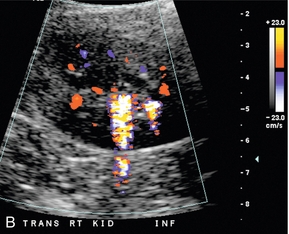

Другой метод допплерографии, помогающий оценить обструкцию мочевыводящих путей, можно провести внутри мочевого пузыря. В случаях с подозрением на почечную обструкцию ультразвуковая оценка струи мочеточника должна быть компонентом ультразвукового исследования почек ( рис. 9-6 ). Хотя поступление мочи в мочевой пузырь не синхронно, обнаружение трех и более струй мочеточника при допплерографии с одной стороны без единого импульса потока с контралатеральной стороны предполагает обструкцию непульсирующего мочеточника.

РИСУНОК 9-6. Нормальная струя мочеточника. Поперечное цветное допплеровское изображение показывает линейную «струю» цвета, выступающую в просвет мочевого пузыря. Это представляет собой быстрый поток мочи в мочевой пузырь вследствие перистальтики мочеточника.